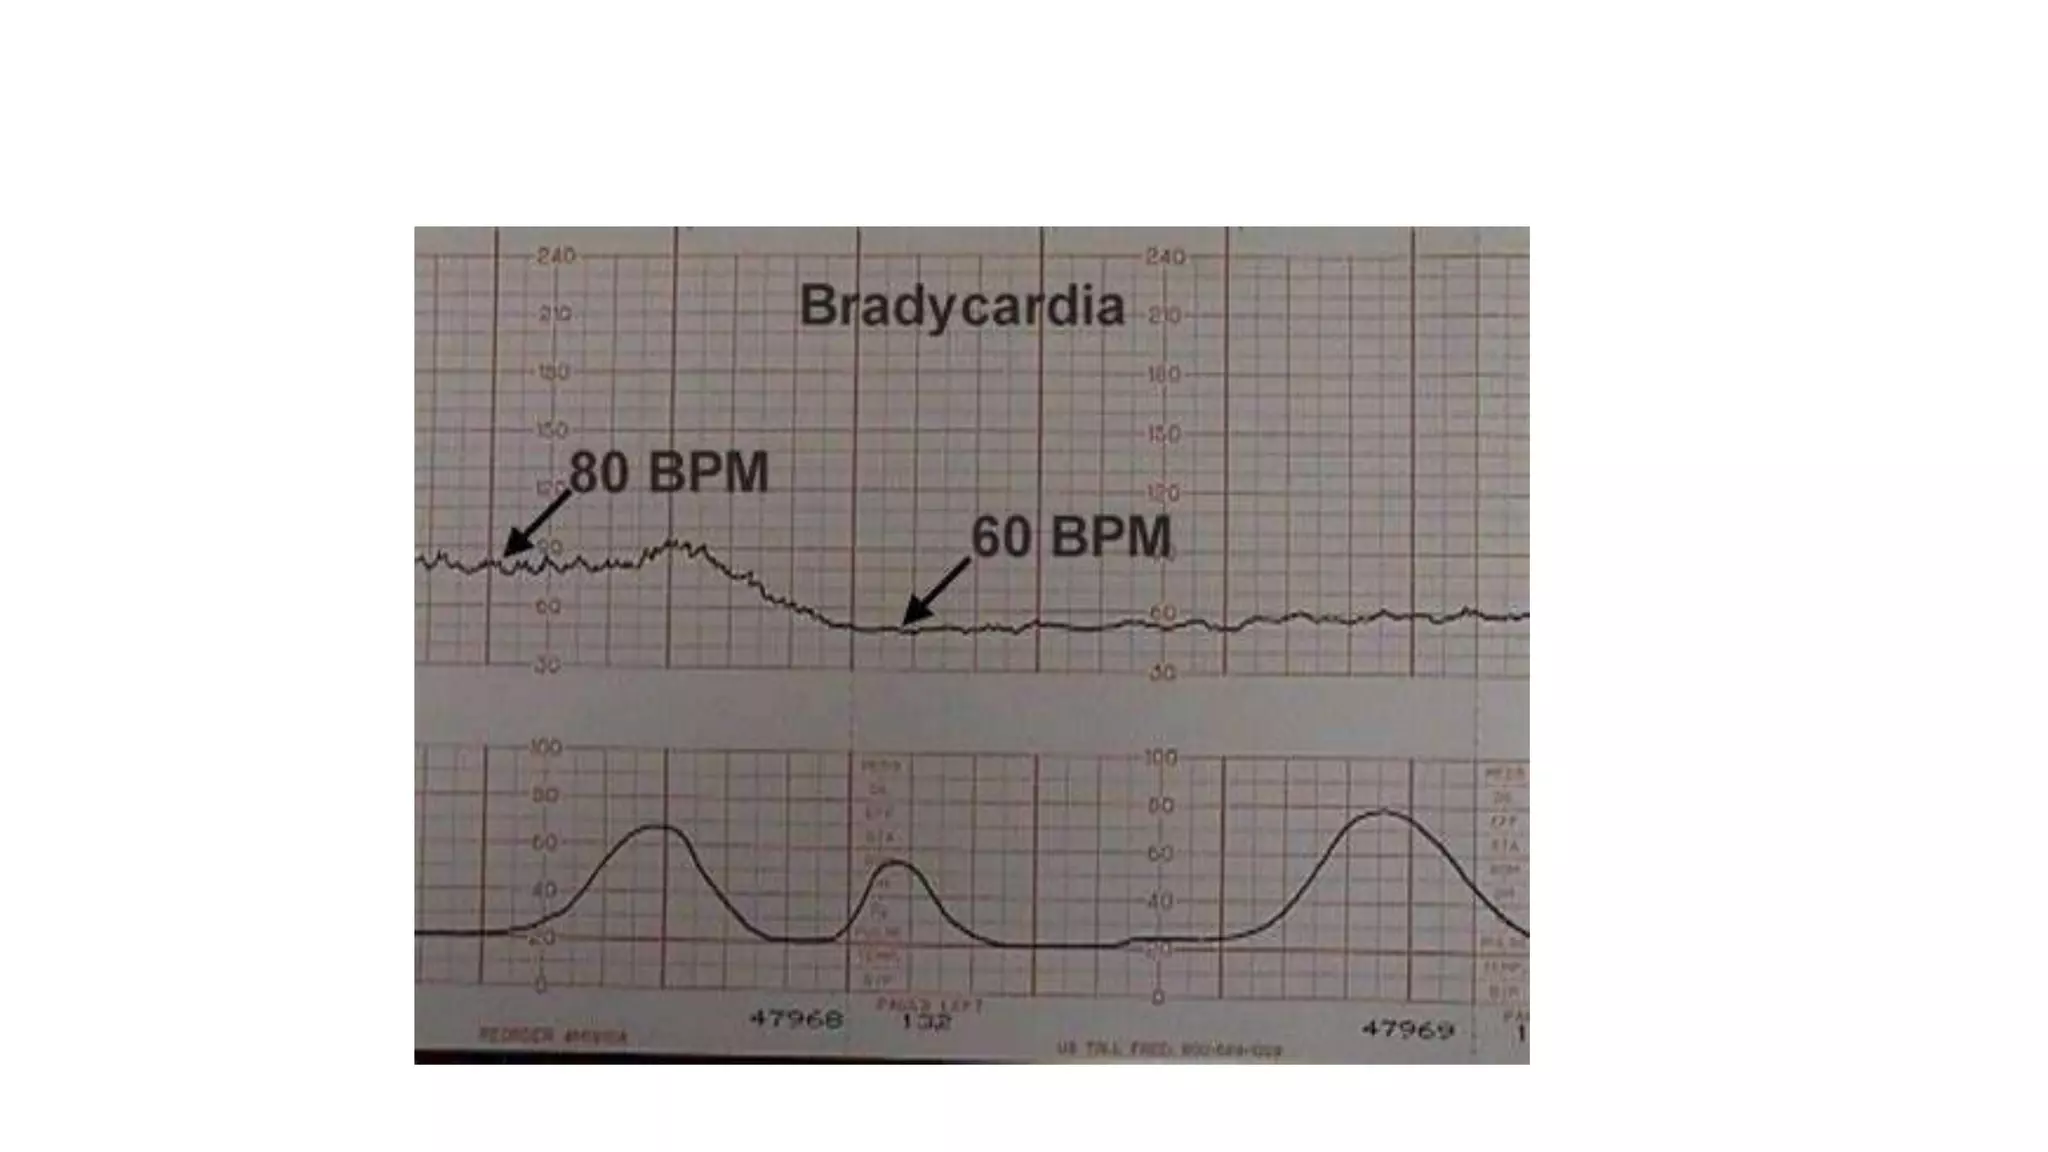

The document discusses key metrics for monitoring a baby's heart rate in utero, including the normal baseline rate of 100-160 bpm and variability. It also covers types of accelerations and decelerations that can occur, such as early or late, as well as bradycardia, which is an abnormally slow heart rate.